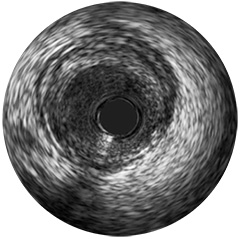

Figura 3